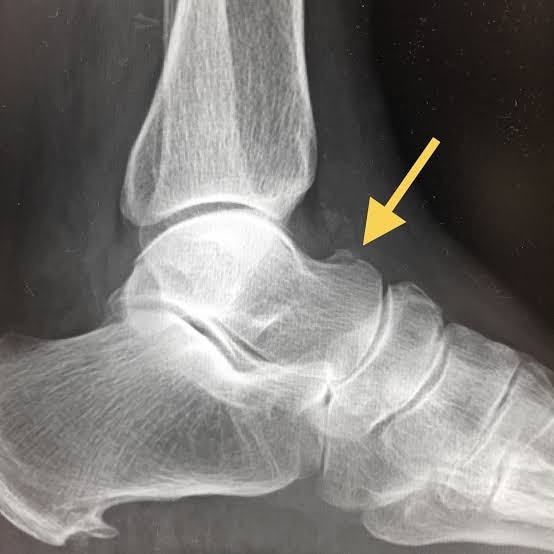

足首の靱帯の見え方を比較

足首のレントゲン画像

骨は綺麗に写っていますが、靱帯はほぼ見えません。